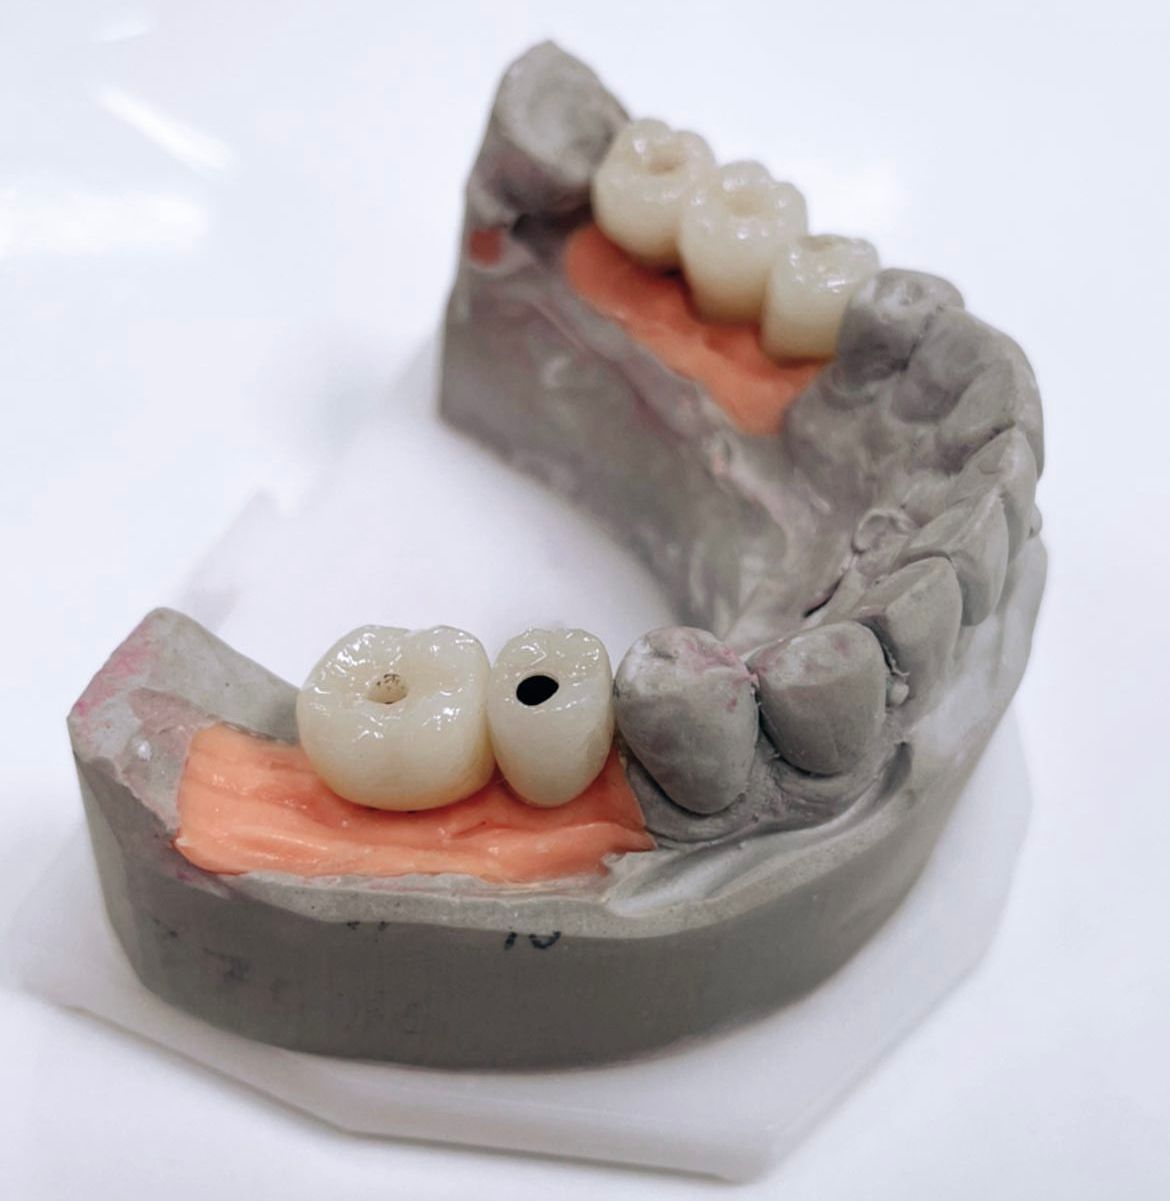

- protetyka (korony ceramiczne (cerkon, E-max), licówki, mosty, protezy ruchome, korony na teleskopach, inlay, onlay, overlay, endkorony);